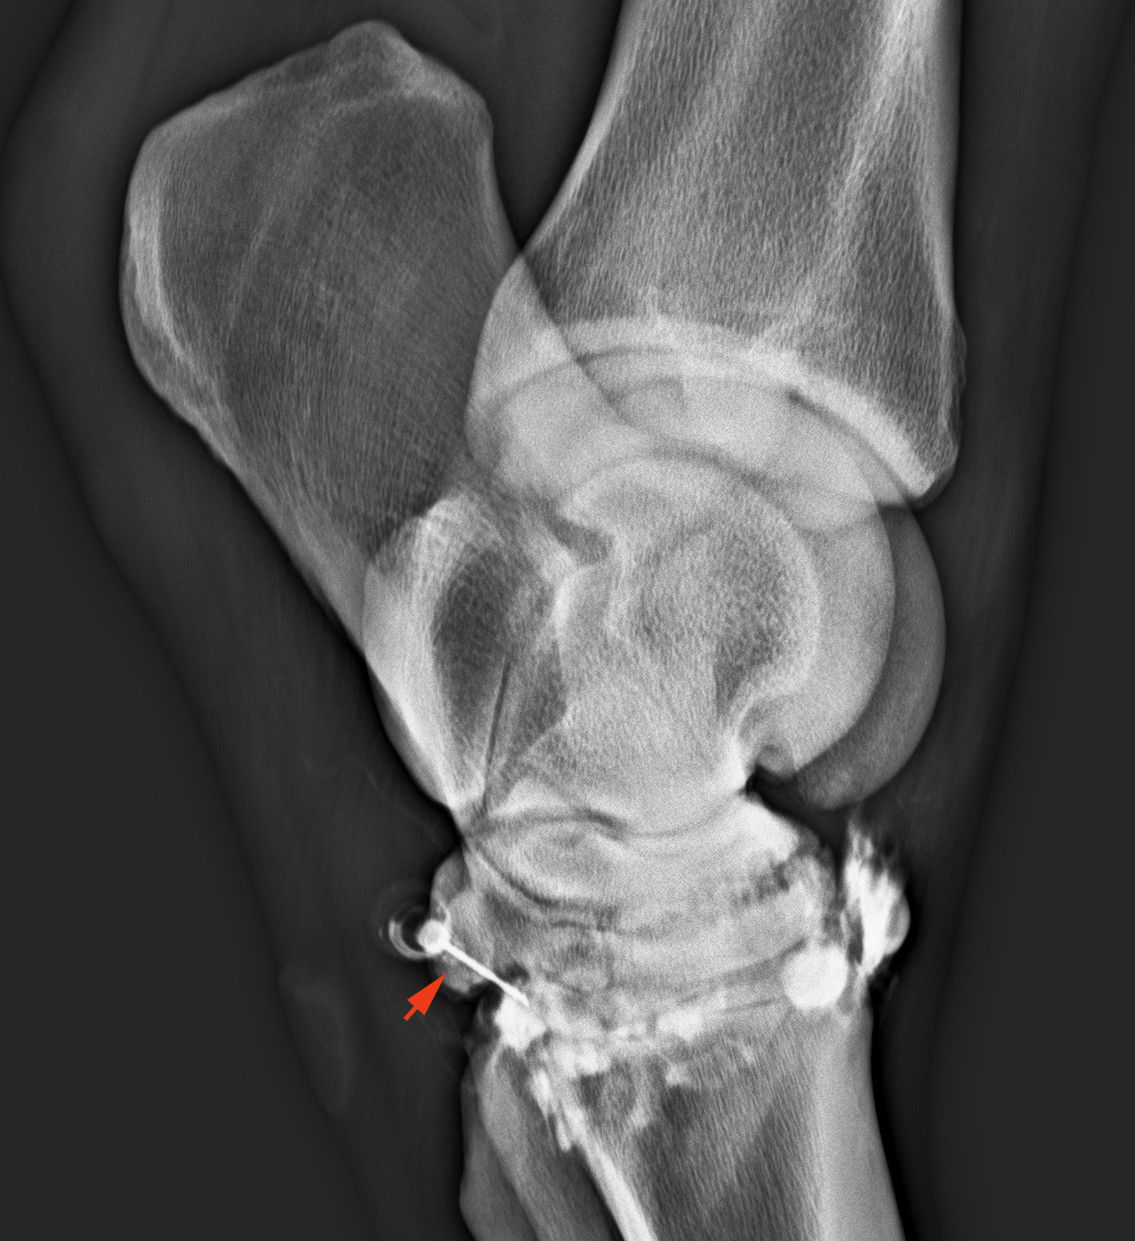

Az ízületbe fecskendezett 70%-os alkohol felgyorsítja a porc kioldódását és gyorsul az összecsontosodás is. Nagyon erős fájdalomcsillapító hatása van, ami miatt már pár nappal a kezelés után sokkal jobban vannak az állatok. A párta- és a csánkízületet szoktuk így kezelni. A csánkízület kezelését kontrasztos röntgenvizsgálat előzi meg, hogy ellenőrizzük, hogy az ízületbe adott alkohol ne jusson a csánk felső részeibe, aminek porckárosítása nem célunk.

Kontrasztanyag fecskendezése az alsó ízületbe. A világítóan fehér kontrasztanyag nem folyik a felső ízületekbe, az eljárás elvégezhető. A nyíl a tűt mutatja, ami végig az ízületben van.